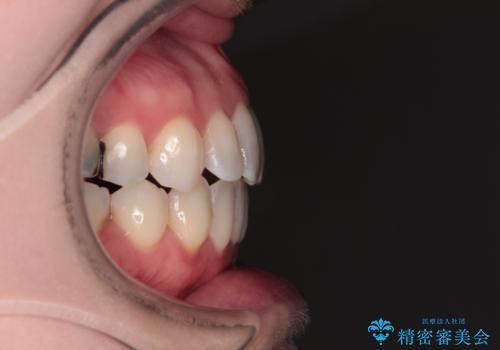

口元の突出感とデコボコがあり、上下左右の小臼歯4本を抜歯して矯正治療を行う方針としました。(右上は欠損のため計3本抜歯)

むし歯となっている歯は状態が悪く、将来的に抜歯となる可能性が高かったため、定石で抜歯させる小臼歯の代わりにむし歯となっている大臼歯を抜歯し、ワイヤー装置にて矯正治療を行うこととしました。